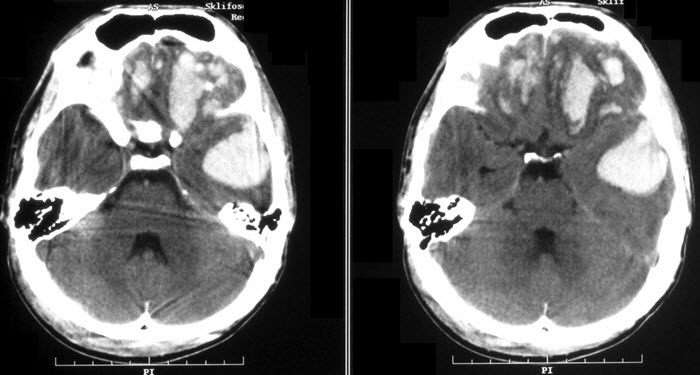

Выраженная и тяжелая ВЧГ, как правило, являются следствием грубой декомпенсированной неврологической патологии (например, при опухоли головного мозга или кровоизлиянии). У детей часто встречается синдром доброкачественной внутричерепной гипертензии, при котором отсутствуют признаки объемного образования мозга или симптомы гидроцефалии. В основном это проявляется легкой и средней степенью повышения интракраниального давления.

- нейровизуализация (КТ и МРТ);